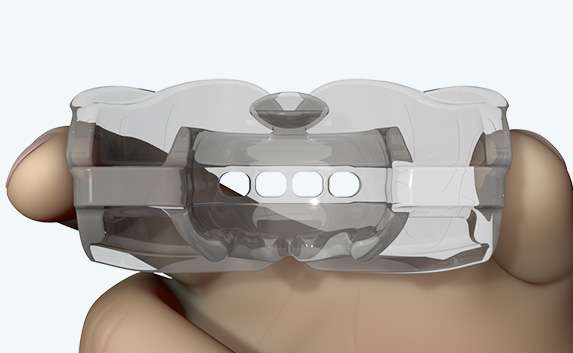

The Myosa®for TMJBDS®S1 is used in patients with a Breath Hold Time (BHT) of 20 seconds or more. It works by advancing the sleeper’s lower jaw and opening the bite, which has the effect of opening the airway. Additionally, the S1 has four breathing holes at the front to regulate breathing. For better retention during sleep, the patient can use the mouldable version of the S1 appliance (S1M). Progress to the S2 when the patient’s BHT reaches 35 seconds or more.